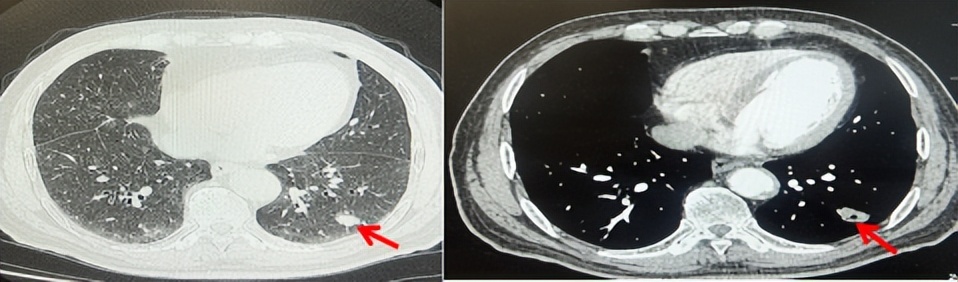

71岁男性,高血压病史20年,口服药物治疗,无糖尿病、心脏病等基础疾病,吸烟史50年,20支/天,已戒1年余,无饮酒史,无肿瘤家族史。2023.11因咳嗽、咳痰行胸CT检查:左肺下叶占位性病变,大小约12mmx8mm(如图5)。2023.11.20行“单孔胸腔镜左肺中下叶切除、肺门及纵隔淋巴结清扫、胸膜粘连松解术”;术后病理:(左肺下叶)结合免疫组化鳞状细胞癌(中、低分化),局部见脉管内癌栓,未见确切神经侵犯,(气管切缘)净。(淋巴结)未见转移癌0/19(4组0/1;5组0/1;6组0/2;7组0/1;9组0/1;10组0/2;11组0/3;12组0/2;13组0/2;14组0/4)。术后分期pT1bN0M0 IA期,术后定期复查。

2024.09.12复查胸部CT示左侧胸膜结节,大者约为27mmx13mm,考虑转移可能性大,纵隔淋巴结增大,恶性?(如图6)。患者行胸膜穿刺活检取病理,结果示(胸膜)结合免疫组化,支持鳞状细胞癌,PD-L1(克隆号28-8)TPS约20%。分期为rT0N2bM1a IVA期,DFS为10个月。2024.09.24起行替雷利珠单抗联合紫杉醇+卡铂方案治疗4周期,复查胸CT评效SD(如图7)。后患者因脑梗塞停止治疗,于综合医院就诊,后未返院复查及治疗。

图5:患者手术前(2023.11)胸部CT肺窗及纵隔窗

图6:患者胸膜及纵隔转移(2024.09)胸部CT肺窗及纵隔窗